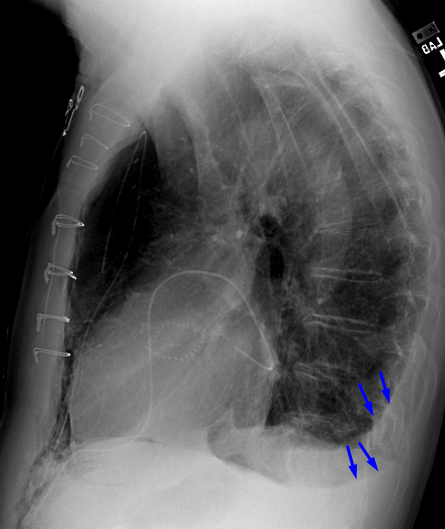

Age: 66

Sex: Male

Indication: Post-op ascending aortic aneurysm repair

Sample ReportModerate-sized right apical pneumothorax. No mediastinal shift.

Pneumomediastinum tracking along the pericardium and extending into the anterior mediastinum.

Small bilateral pleural effusions.

Hazy bibasilar opacities likely represent atelectasis in this postoperative patient.